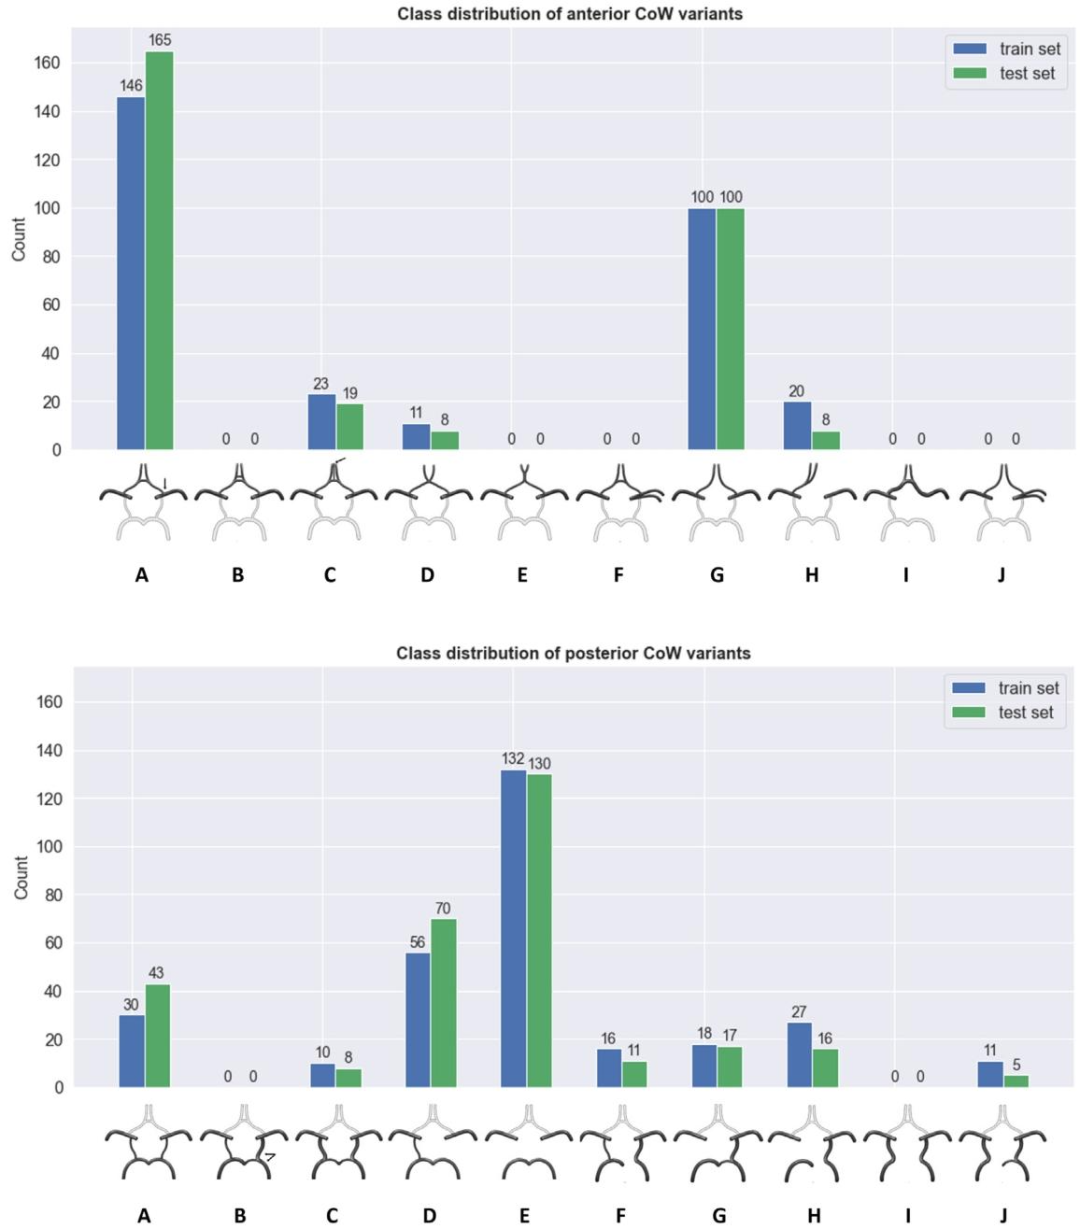

Fig. 3. Class distribution of training and test cases for Task 1. Anterior part: A, single anterior communicating artery (AcoA); internal carotid artery (ICA) bifurcates intoprecommunicating anterior cerebral artery segment (A1-ACA) and middle cerebral artery (MCA). B, Two or more AcoAs. C, Medial artery of corpus callosum arises from AcoA (3A2 segments). D, Fusion of ACAs over short distance. E, ACAs merge into common trunk, then split distally. F, MCA originates as two separate trunks from ICA. G, Hypoplasiaor absence of AcoA. H, One A1-ACA hypoplastic or absent. I, Hypoplasia or absence of ICA. J, Hypoplasia or absence of AcoA; MCA arises as two separate trunks. Posterior part:A, Bilateral posterior communicating arteries (PcoAs) present. B, Posterior cerebral artery (PCA) originates mainly from ICA, known as unilateral fetal-type PCA; opposite PcoAis patent. C, Bilateral fetal-type PCAs with both precommunicating segments (P1-PCAs) patent. D, Unilateral PcoA present. E, Hypoplasia or aplasia of both PcoAs. F, Unilateralfetal-type PCA and hypoplasia or absence of the P1-PCA. G, Unilateral fetal-type PCA and hypoplasia or absence of the contralateral PcoA. H, Unilateral fetal-type PCA andhypoplasia or absence of both a P1-PCA and PcoA. I, Bilateral fetal-type PCAs with hypoplasia or absence of both P1-PCAs. J, Bilateral fetal-type PCAs with hypoplasia or absencof one P1-PCA.

图3. 任务1训练集和测试集的类别分布 前部: A. 单一前交通动脉(AcoA);颈内动脉(ICA)分叉为交通前大脑前动脉段(A1-ACA)和大脑中动脉(MCA)。 B. 两条或更多前交通动脉。 C. 胼胝体 medial 动脉起自前交通动脉(3个A2段)。 D. 大脑前动脉(ACAs)在短距离内融合。 E. 大脑前动脉合并为共同主干,随后在远端分叉。 F. 大脑中动脉从颈内动脉以两个独立主干发出。 G. 前交通动脉发育不全或缺失。 H. 一侧A1段大脑前动脉(A1-ACA)发育不全或缺失。 I. 颈内动脉发育不全或缺失。 J. 前交通动脉发育不全或缺失;大脑中动脉以两个独立主干发出。 后部: A. 双侧后交通动脉(PcoAs)存在。 B. 大脑后动脉(PCA)主要起自颈内动脉(称为单侧胚胎型大脑后动脉);对侧后交通动脉通畅。 C. 双侧胚胎型大脑后动脉,且双侧交通前段(P1-PCAs)均通畅。 D. 单侧后交通动脉存在。 E. 双侧后交通动脉发育不全或未发育。 F. 单侧胚胎型大脑后动脉,且该侧P1段大脑后动脉(P1-PCA)发育不全或缺失。 G. 单侧胚胎型大脑后动脉,且对侧后交通动脉发育不全或缺失。 H. 单侧胚胎型大脑后动脉,且该侧P1段大脑后动脉和后交通动脉均发育不全或缺失。 I. 双侧胚胎型大脑后动脉,且双侧P1段大脑后动脉均发育不全或缺失。 J. 双侧胚胎型大脑后动脉,且一侧P1段大脑后动脉发育不全或缺失。